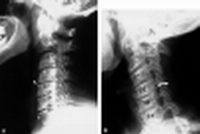

| Prior imaging | oldest & most recent |

| Location | E.g. proximal, middle, distal third |

| Bodies | Height, trabeculations |

| Disks | Height, |

| Odontoid | #'s, dens-anterior arch distance (adults: < 3 mm; peds: < 5 mm) |

| Lines | Anterior spinal line, posterior spinal line, spinolaminar line, clivus base line |

| Lordosis | |

| Soft tissue swelling | Retropharyngeal, retroesophageal |

| Degenerative disk disease (DDD) | ↓ disk space osteophytes borders of adjac vert bodies may vacuum phen |

| DISH | flowing ossifn >= 4 contig verts no facet or SIJ ankylosis rel minimal DDD |

| Spondylosis deformans | ant & lat osteophytes rel preserved disk spaces |

| Facet DJD | osseous facet overgrowth ↓ jt space sclerosis |

Facet DJD + DDD may → degen spondylolisthesis